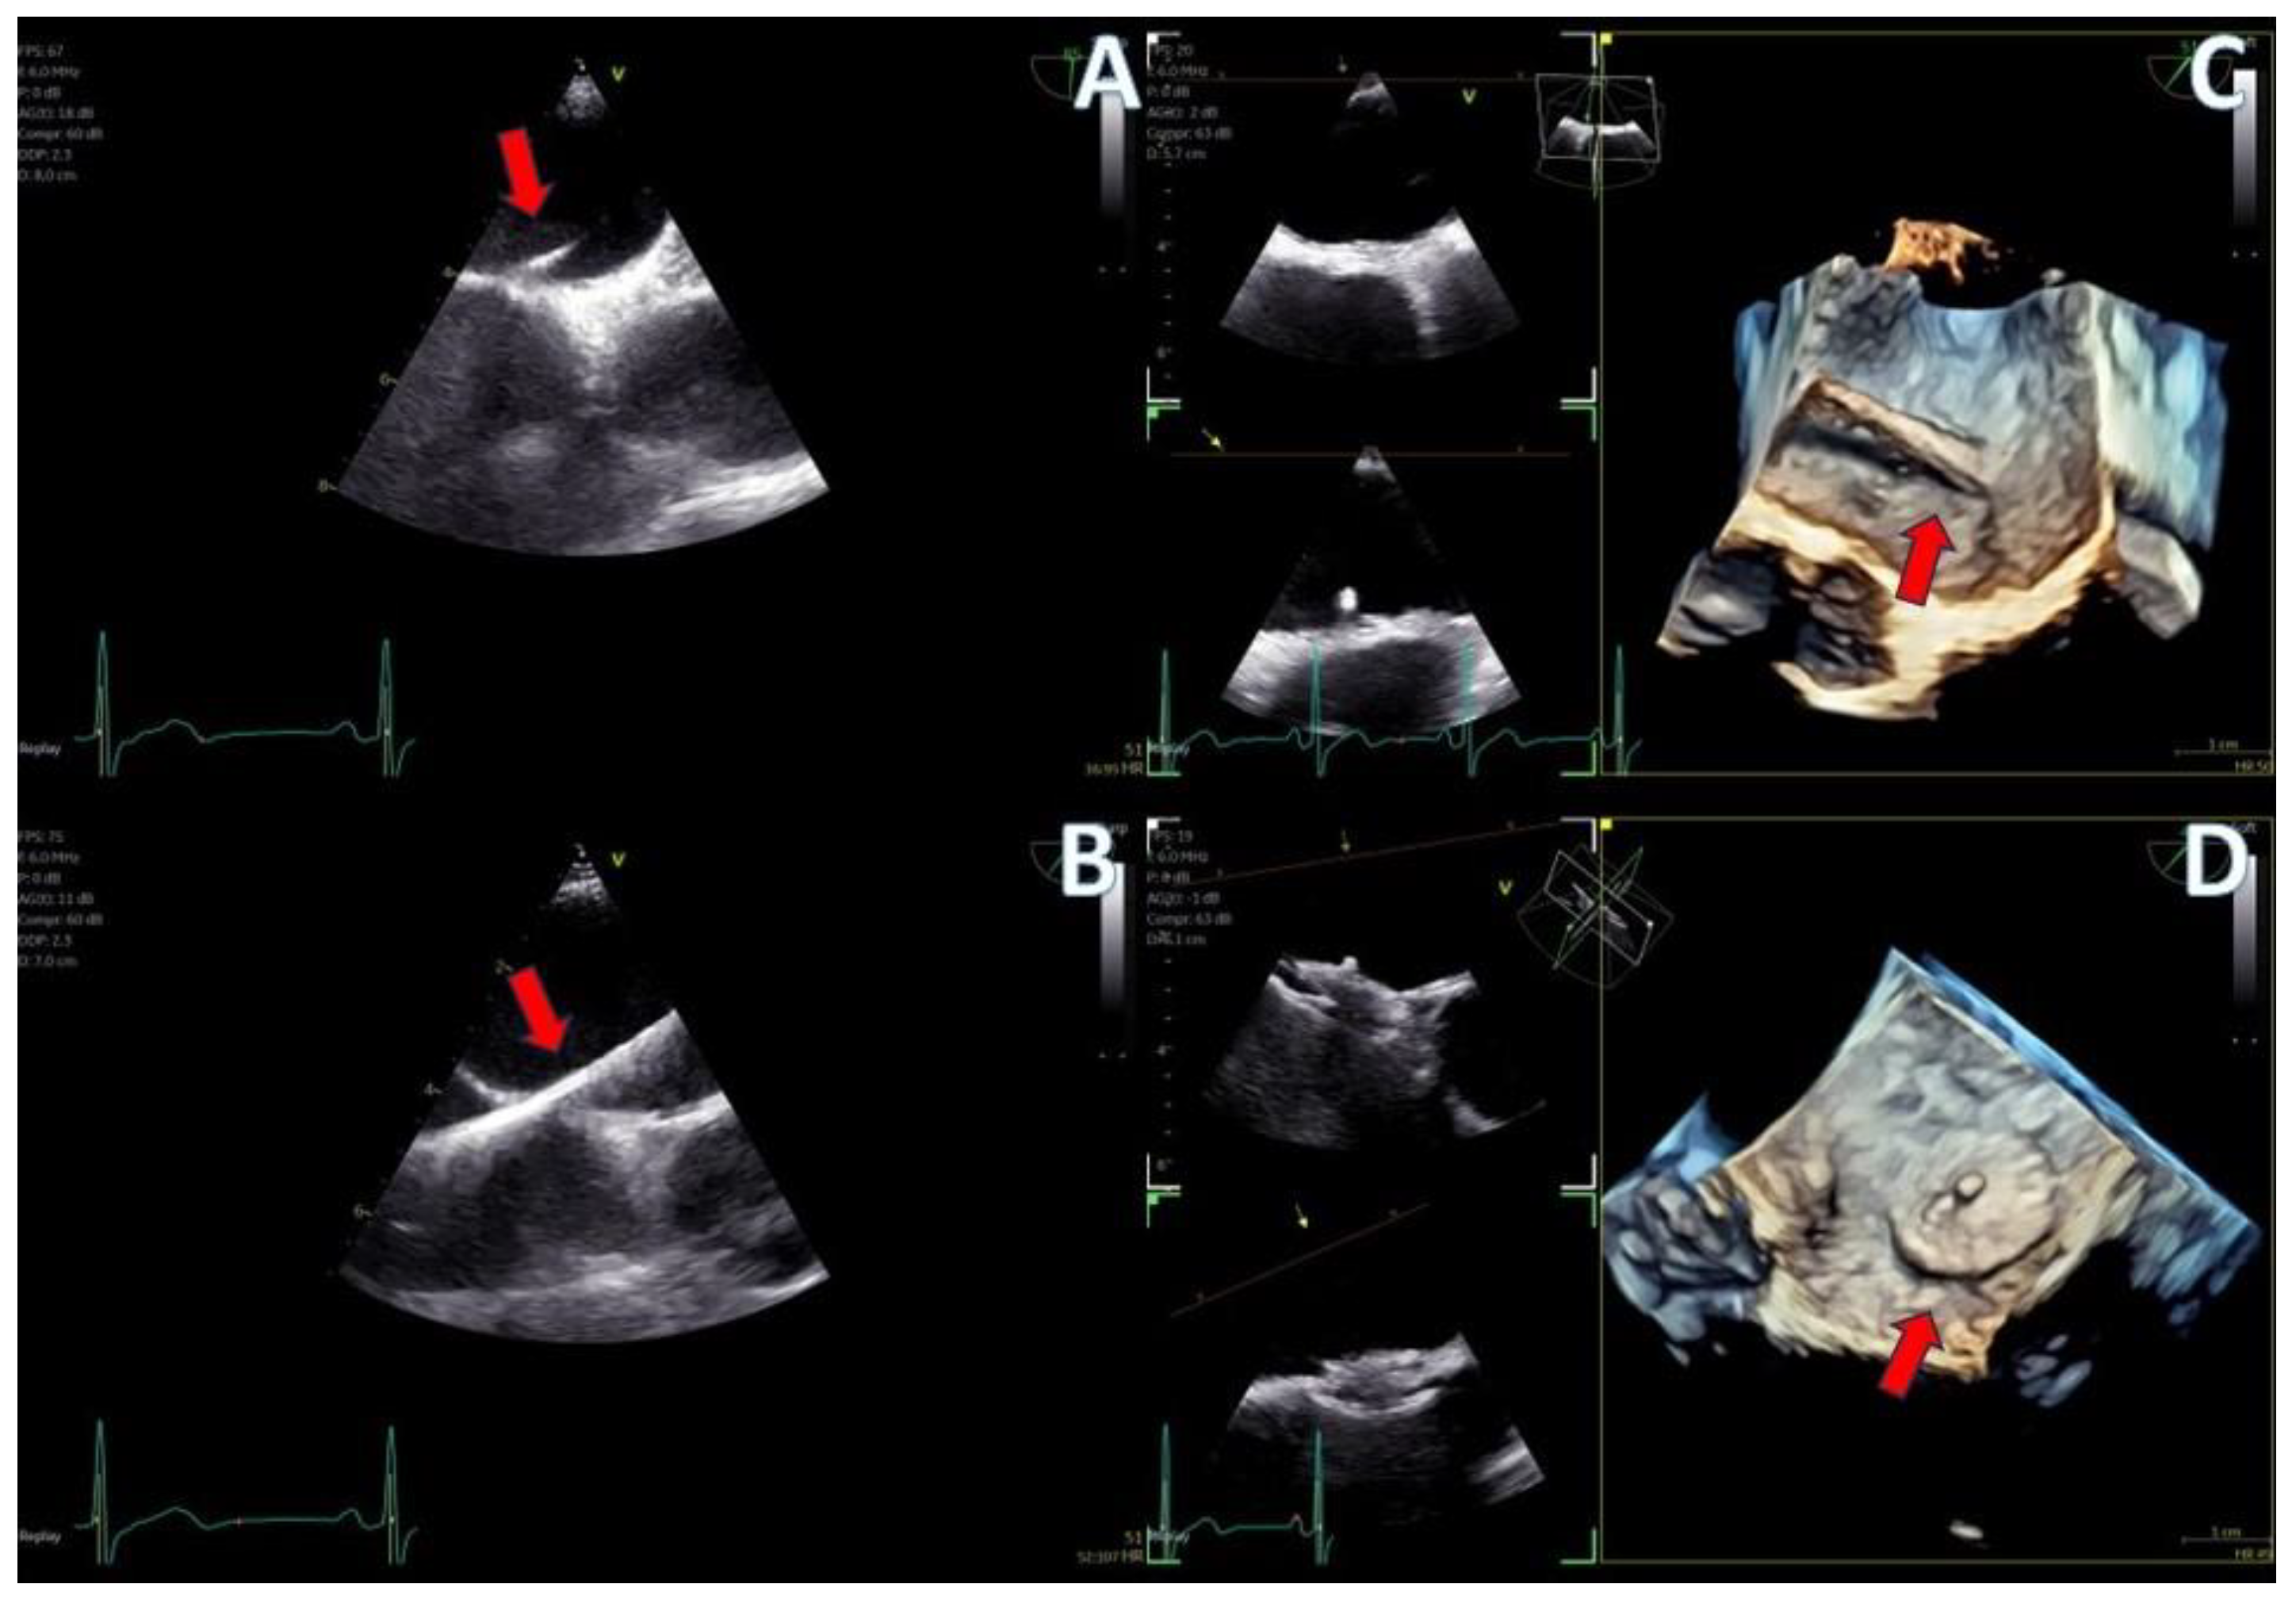

Figure 8.

LAA closure case; (A) biplane images of the LAA showing the presence of distal thrombus (red arrow), (B) measurements of the ostium and the landing zone with biplane imaging, (C) Biplane images of the implanted AMULET device (red arrow), (D) 3D volume−rendered image showing a view of the implanted AMULET device (red arrow).

Figure 9.

PFO closure case; (A) J wire through the PFO tunnel (red arrow), (B) stiff wire for guidance through the PFO tunnel (red arrow), (C) 3D volume−rendered view of the guide catheter through the PFO tunnel (red arrow), (D) final result with left atrial view of the PFO Amplatzer occluder (red arrow).

In the case of LAA closure (Figure 8, video S3), 3D tools (MPR-flexislice) aided in accurate sizing of the ostium and the landing zone (important for AMULET device), particularly in the presence of distal thrombus where contrast infusion was contraindicated. The final result was satisfactory, with no leakage observed and a stable device placement was confirmed with a tug test.

PFO closure cases (Figure 9, video S2) benefited from the probe’s excellent imaging, enabling precise wire insertion and providing anatomical criteria for device sizing. A bubble contrast study was performed at the beginning and at the end of the procedure for any remaining shunt. The stability of the device was confirmed with a wiggle test. Similarly, in the ASD case (Figure 7, video S1), the probe facilitated visualization of all defect rims and accurate sizing of the oval-shaped defect (with MPR) confirmed with balloon sizing and stop-flow technique and ensured a successful outcome with no residual shunt observed.